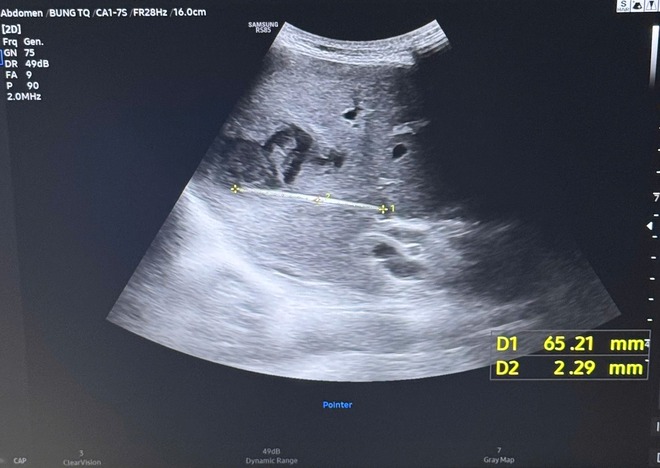

Cây tăm được bác sĩ gắp ra (bên trái) và hình ảnh cây tăm qua siêu âm (bên phải)

Khi tiến hành siêu âm chi tiết hơn, ê-kíp điều trị phát hiện một dị vật cản quang xuyên trong nhu mô gan, dài khoảng 6–7cm. Kết quả chụp cắt lớp vi tính (CT scan) ổ bụng sau đó xác định có một dị vật dạng que dài nằm hoàn toàn trong gan, kèm theo ổ áp xe sâu.